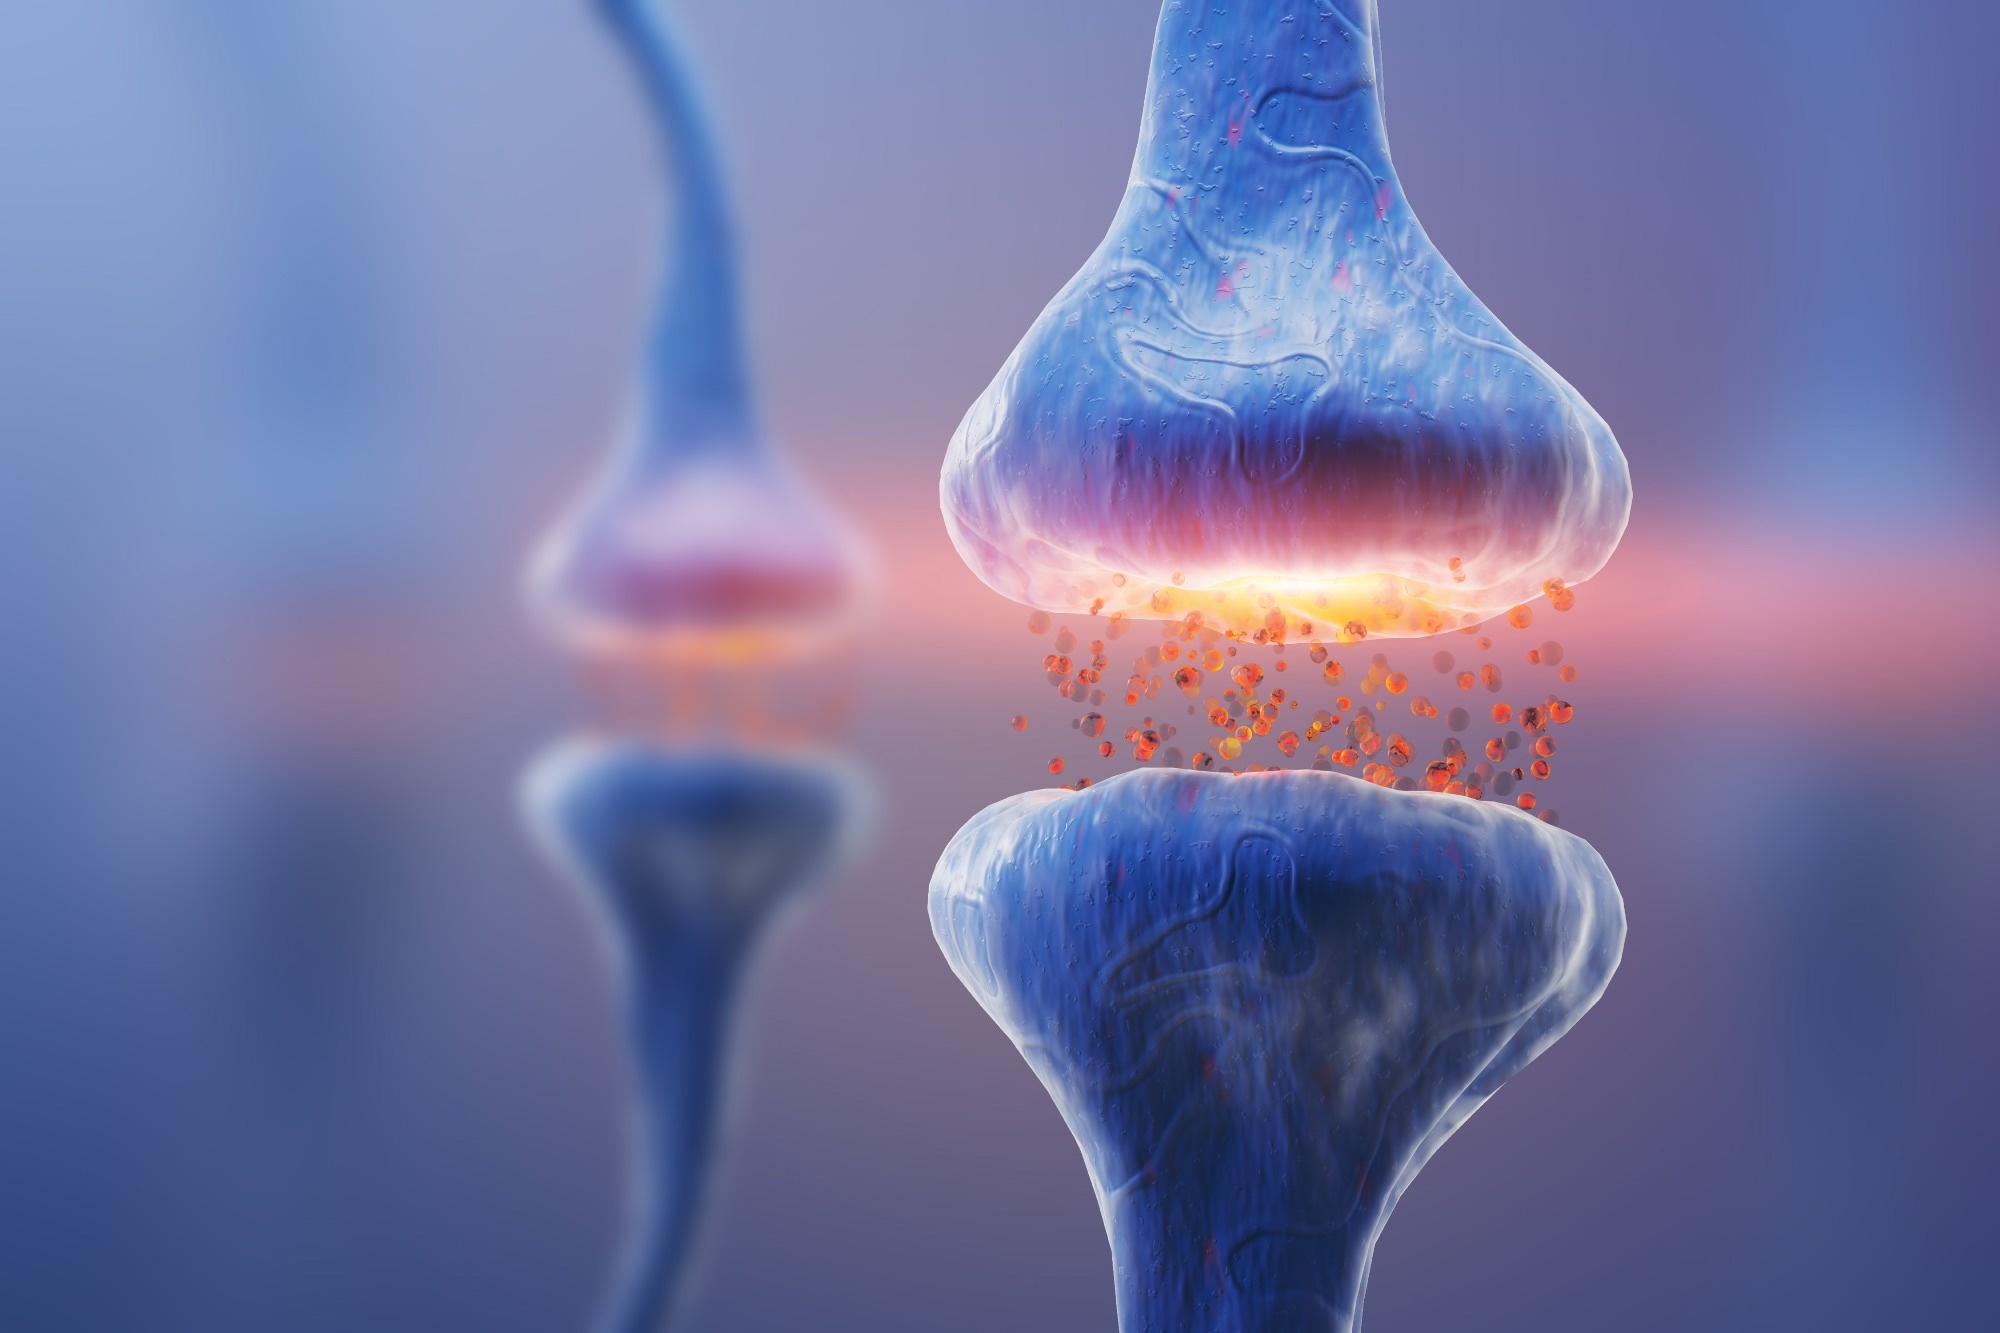

There are three modes of neurotransmission: stimulation-dependent release (evoked), asynchronous evoked release, and spontaneous release.

The stimulation-dependent release is tightly connected with incoming action potentials, which means that when an action potential is received, synaptic vesicles fuse with the presynaptic membrane practically instantly, releasing neurotransmitters. It is like runners starting as soon as the start gun goes off; the motion is instantaneous and synchronized.

Asynchronous evoked release occurs in response to an action potential, albeit with a delay. It is less temporally related to action potential, similar to runners who did not get off to a fast start. This form of release has a more flexible time.

In contrast, spontaneous release is fully independent of action potentials. Even without stimulation, synaptic vesicles can fuse with the membrane and release neurotransmitters. This is a background process that occurs in the absence of any immediate stimulus from the neuron's electrical activity.

Image Credit: KateStudio/Shutterstock.com